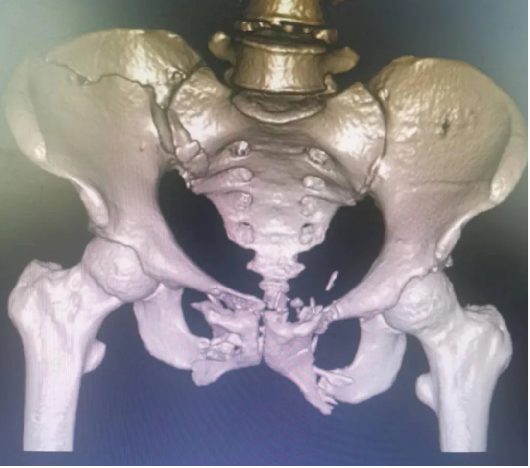

患者因外伤致骨盆前环骨折,患者难以忍耐长期卧床及疼痛,要求行手术治疗以期早日自主翻身坐立活动。

案例三

创伤性骨盆骨折致尿道断裂患者,膀胱造瘘术后,需稳定骨折端避免二次伤害。

骨盆前环微创经皮内固定技术(INFIX技术)固定结合了内固定和外固定的优点,扬长避短,针对此类患者,有效避免了术后深部感染,又避免了使用外固定的手术并发症,让患者在最佳治疗时机获得了骨盆环的稳定,并能早期开始功能锻炼,最大程度上降低了因伤致残的机率。